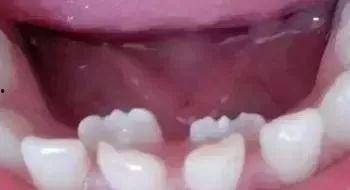

首先,我们要了解什么是牙胚。牙胚是牙齿发育的最初形态,它存在于我们的牙槽骨中。在婴儿时期,我们的牙齿就是从牙胚发育而来的。但是,随着年龄的增长,我们似乎已经告别了长牙的日子。那么,成人怎么长出牙胚呢?

视频中,我们看到了牙胚从牙槽骨中逐渐发育,最终形成完整的牙齿。这个过程虽然复杂,但在视频的讲解下,却显得如此简单易懂。